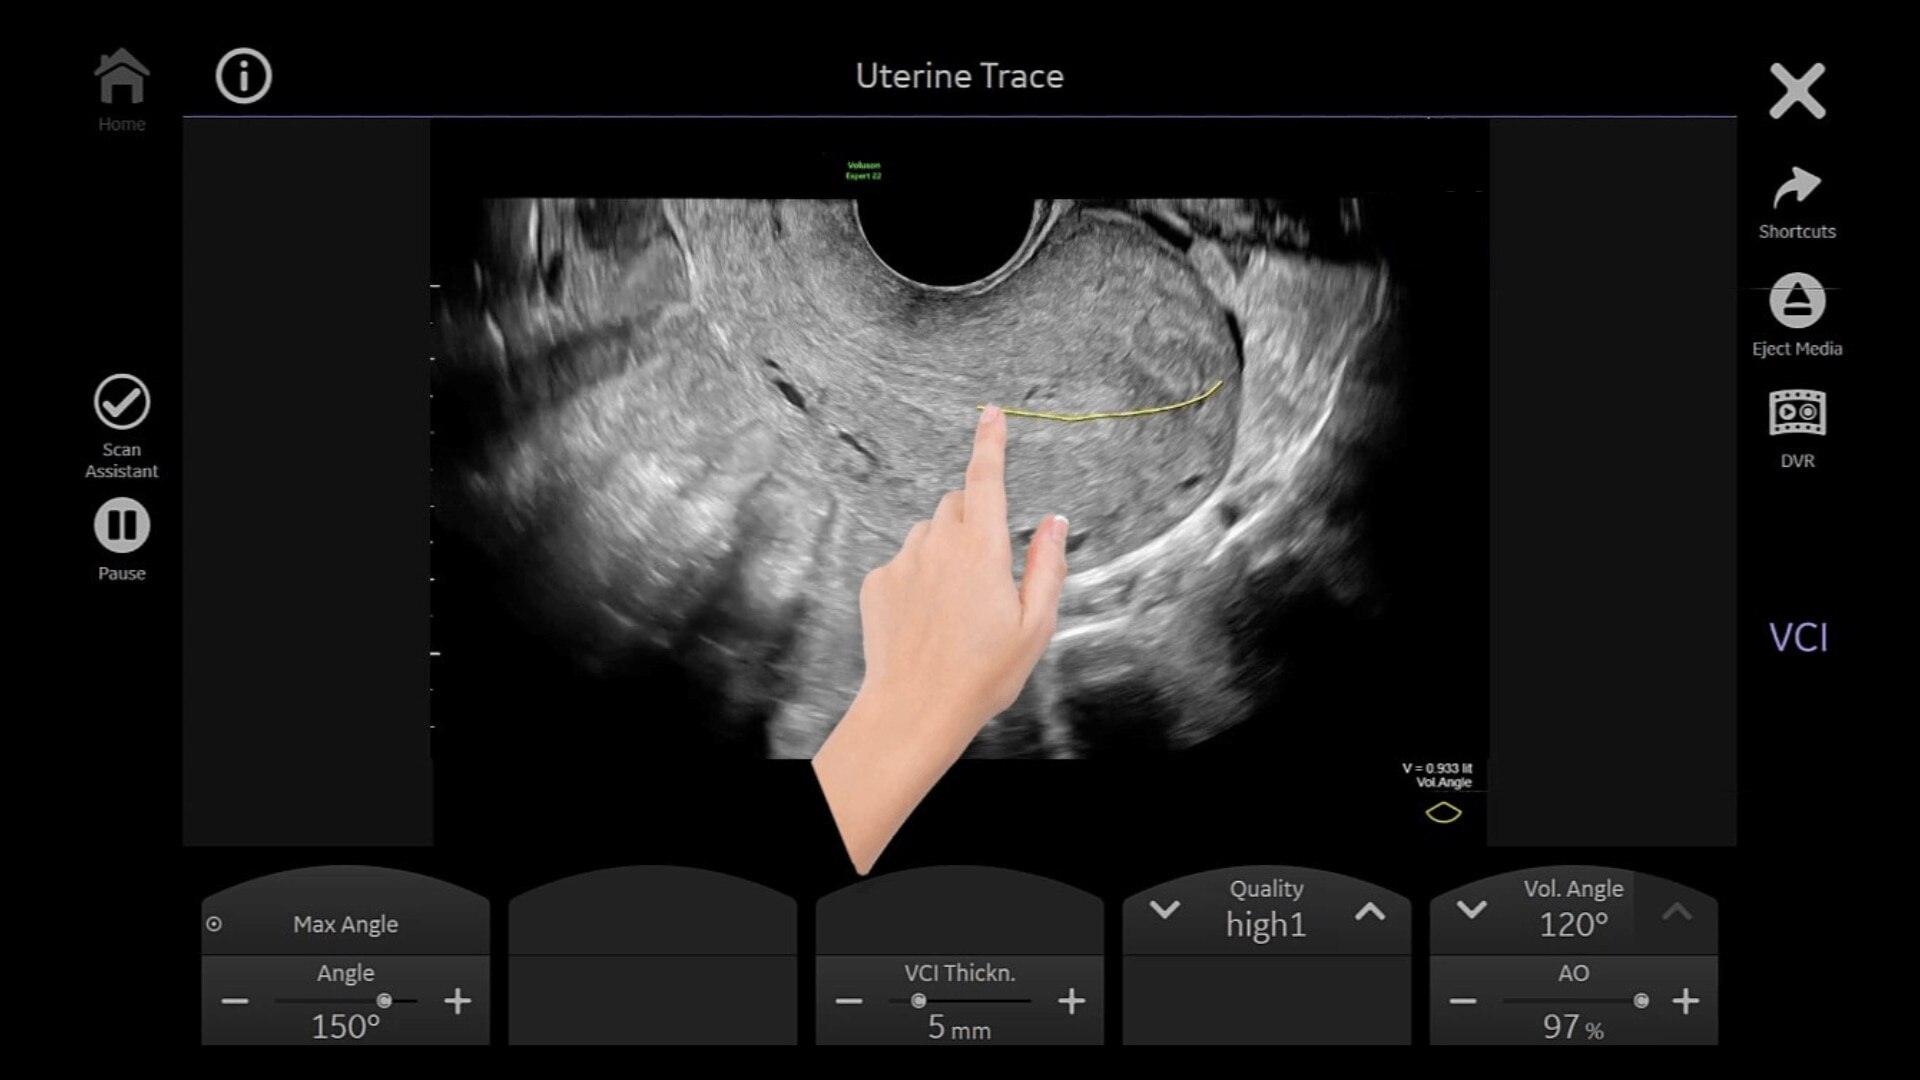

Uterine Trace

Easy display coronal view of uterus.

• Uterine Trace acquires the volume & then displays the coronal view of the uterus to simplify identification & reporting of uterine malformations.

• Easy, accessible 3D for simple, efficient gynecology exams

• Adding 3D can provide more information to help inform your diagnosis and treatment plan. With a comprehensive set of 3D tools, you’ll have everything you need to easily obtain views not possible with standard 2D views.

• Uterine Trace acquires the volume and then displays the coronal view of the uterus linking to ASRM, ESHRE and ESGE Uterine Classification guidelines to simplify identification and reporting of uterine malformations